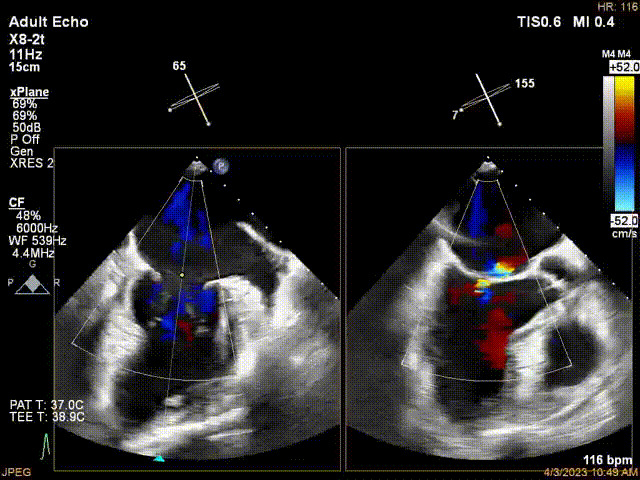

術前超聲提示二尖瓣重度反流

接受治療的是一例器質性重度二尖瓣反流(DMR)患者,主訴“反復活動后胸悶,氣促3年余”。術前超聲顯示,雙房增大,二尖瓣脫垂伴重度反流,輕度三尖瓣反流,輕度肺高壓,升主動脈增寬。手術經股靜脈-房間隔入路,采用全身麻醉插管,在TEE和DSA引導下完成房間隔穿刺。置入JensClip瓣膜夾系統后,在左房調整瓣膜夾的位置和軸向,后進入左室,在TEE引導下捕捉二尖瓣前后瓣葉,并關閉瓣膜夾。經TEE反復確認手術效果后最終鎖定并釋放瓣膜夾。術后即刻超聲顯示瓣膜夾位置穩定,功能良好,術前二尖瓣反流4+,術后0反流,肺靜脈逆流和左房壓都顯著好轉,手術圓滿成功(以上數據都來源于醫院的臨床記錄)。術后患者狀態良好,目前已安排出院。